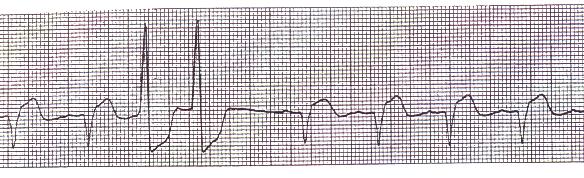

4. Bigeminy PVCs (every other beat is a PVC)

Bigeminy PVCs (every other beat is a PVC)

5. Runs of two (2) or more PVCs in a row.